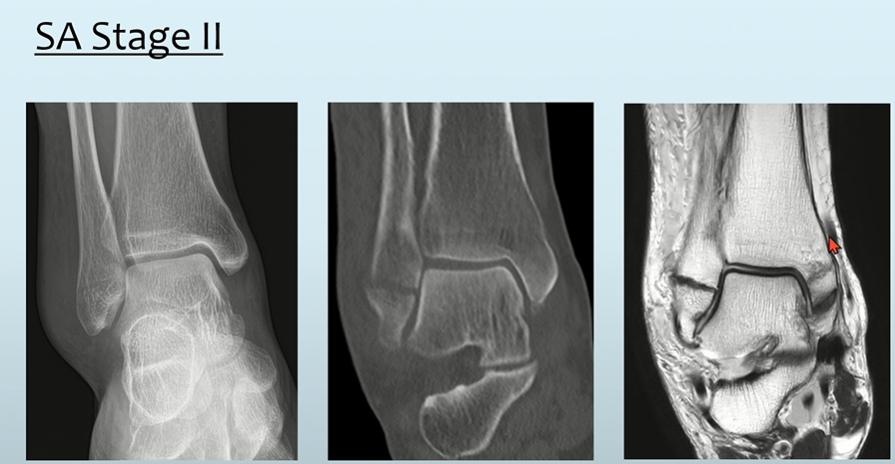

SA type = distal fibula의 transverse한 골절 양상( Danis-Weber classification상 A ) + MM의 vertical한 골절

실제 사진을 보아도 특징적인 모습을 볼 수 있습니다.